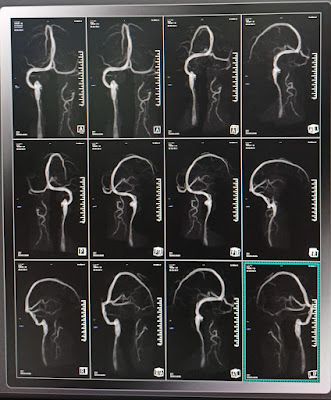

7.MRV image

| MRV images |